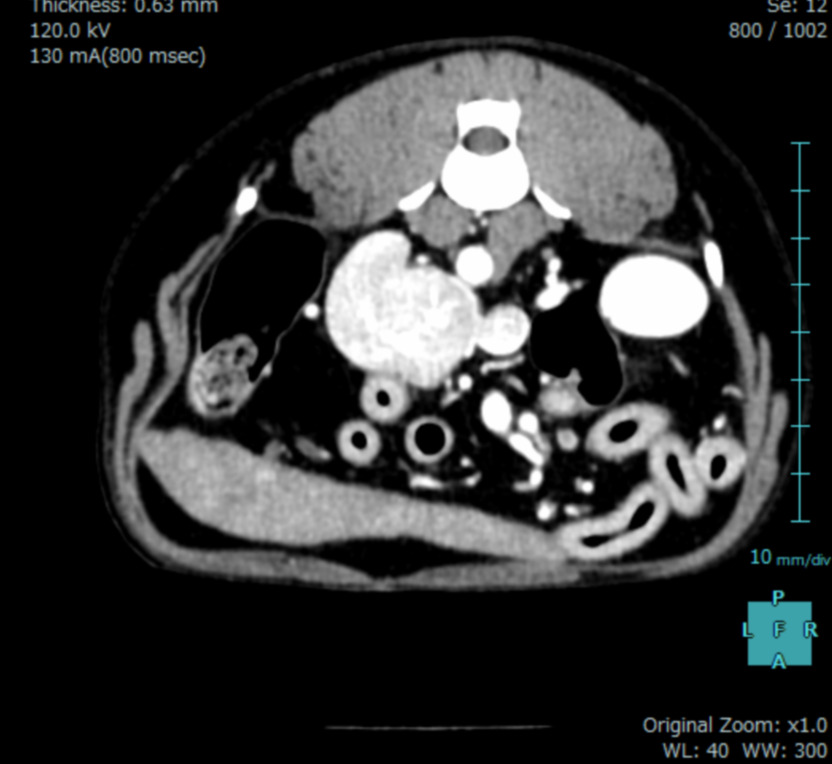

CT検査

麻酔が必要ですが、超音波検査よりも詳細に、副腎の大きさや形、周囲の血管との位置関係や浸潤の有無の判定が可能です。手術計画を立案するうえで必要不可欠な検査であり、造影CT検査は腫瘍の種類の鑑別に役立つ場合があります。